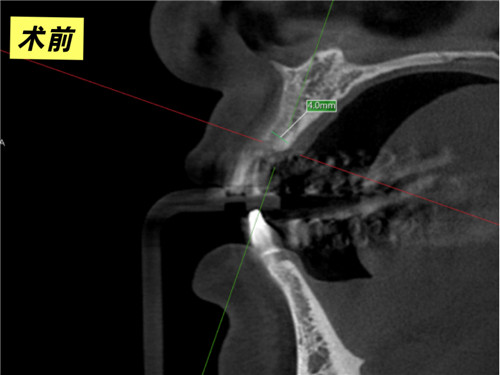

口腔科主任牛躍、副主任醫(yī)師鮑磊接診后,為其完善術(shù)前CBCT(口腔頜面錐形束CT)檢查,細(xì)致評(píng)估口腔條件,發(fā)現(xiàn)患者牙槽骨吸收嚴(yán)重,骨厚度僅4mm,術(shù)中需要植入人工骨粉。在征得患者同意后,科室團(tuán)隊(duì)精準(zhǔn)操作,術(shù)中植入骨粉并覆蓋骨膜,僅用30分鐘便成功完成手術(shù)。3個(gè)月后復(fù)查CBCT,植體與周圍骨質(zhì)結(jié)合良好,科室團(tuán)隊(duì)行牙冠修復(fù)后,患者對(duì)最終效果非常滿意,重新綻放自信笑容。